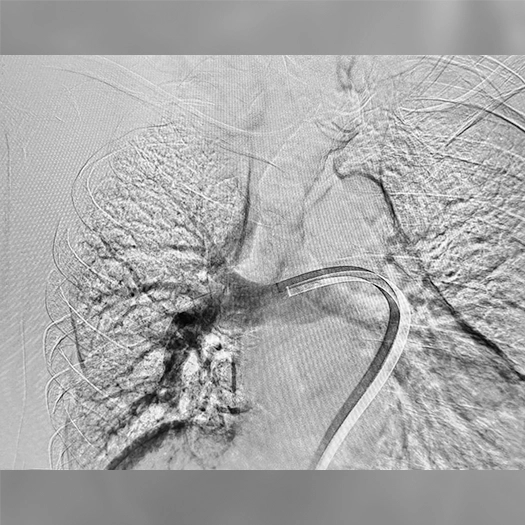

Pulmonary Embolism Cases

Images used with permission and provided for illustrative purposes only. Procedural techniques and decisions based on physician’s medical judgment. Individual results may vary. Consents on file at Penumbra, Inc.